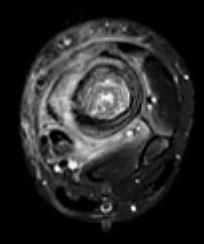

问题 男,33岁,有发热,小腿局部有疼痛,红肿并有压痛,请结合图像,选择最佳答案 ( )

选项 A、骨髓瘤 B、骨化性肌炎 C、脂肪瘤 D、未见异常 E、骨髓炎

答案 E